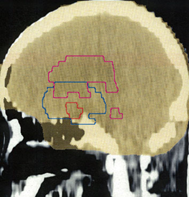

ここには,脳腫瘍の治療で良く用いられる(拡大)局所照射,全脳室系照射,全脳照射の治療計画と脳にあたる線量の分布を図にしてあります。実際に視床下部/下垂体にできた胚腫ジャーミノーマの患者さんに,25.2グレイを14回に分割してかける計画を立てた時のものです。上から順に局所照射,全脳室照射,全脳照射となっていますから,この照射がどのようなものかを理解する手がかりにしてください。青い線はCTV,黄色く塗ったのはPTVです。

全脳照射

全ての脳に25.2グレイが入ります。脳の100%の容積に25.2グレイが入っています。全脳室系照射と全脳照射が変わらないという意見も時々聞きますが,全脳室で照射が入らない部分を見るとかなり違っていることが判ります。海馬だけ外すような治療計画 hyppochanpal avoidant RT が用いられる傾向にあります。